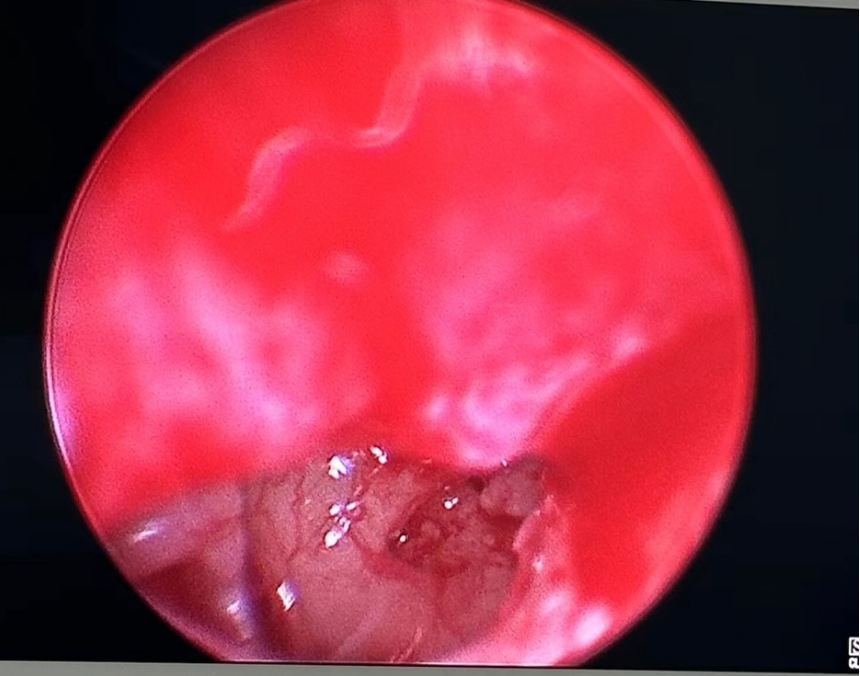

考虑到病友眩晕明显,佘万东团队进行了商讨,决定先给予耳后注射激素,继续输液,同时排除合并耳石症的可能,观察治疗1周后,依然眩晕没有任何好转。佘教授和患者家人充分沟通交流后,决定行微创下中耳探查,观察有无可能发生了圆窗膜破裂(俗称第二鼓膜),最后术中还是发现圆窗处总是有透亮的光点,考虑圆窗膜破裂导致了患者持续的眩晕耳聋,并给予相应的处理。术后一周,患者的眩晕耳鸣耳聋耳闷均有改善,自己下床行走。出院后不到一周,患者高兴地打电话给了佘教授。